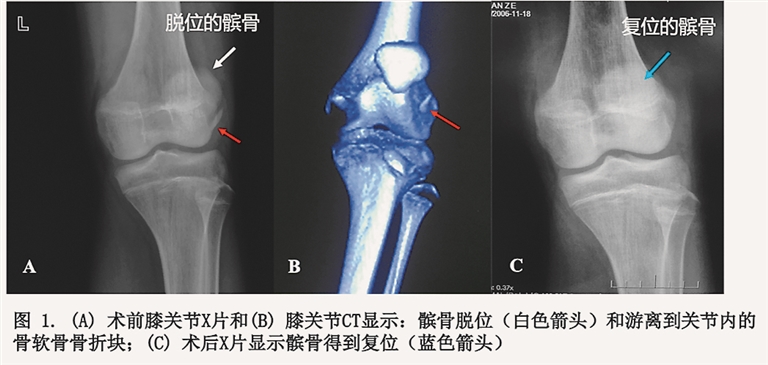

19日,小郭来到哈医大一院群力院区骨二科病房。住院后,李贵东副主任医师带领的关节、运动医学团队,经过查体和阅片诊断他为“急性创伤性髌骨脱位、MPFL(内侧髌股韧带)髌骨止点断裂合并髌骨骨软骨骨折、多发关节松弛症”,给予制动、支具固定、局部冰敷、镇痛等处置的同时,进行下肢三维重建CT确认有合并下肢力线不良、髌股关节畸形等固有因素。急性髌骨脱位合并游离骨软骨折,越早手术效果越好,李贵东医师团队在精心术前准备后,于22日对郭某进行了关节镜下探查,游离骨软骨块取出,复位固定,MPFL骨锚钉修复术。术后,小郭按照医生的指导正进行着早期康复锻炼。